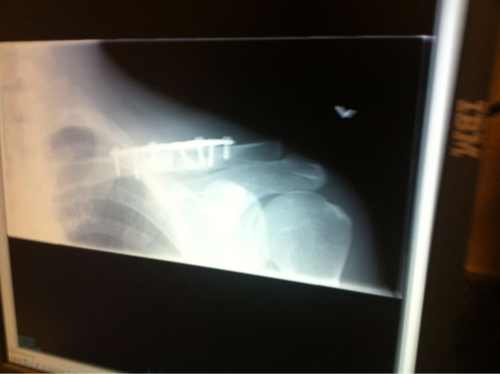

clavicle

A Clavicle is a Terrible Thing to Taste